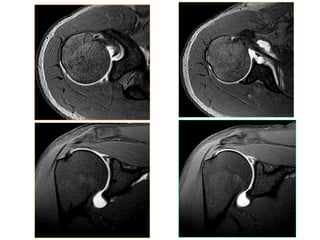

PROTOCOL CHUÏP KHÔÙP VAI

* Khoâng tieâm thuoác töông phaûn noäi khôùp:

- Axial + Coronal Oblique + Sagittal Oblique T2FS,

PdFS

- Coronal T1W

- Ñoä daøy laùt caét # 3mm

- Dist. Factor # 10%

* Coù tieâm thuoác töông phaûn noäi khôùp:

T1FS